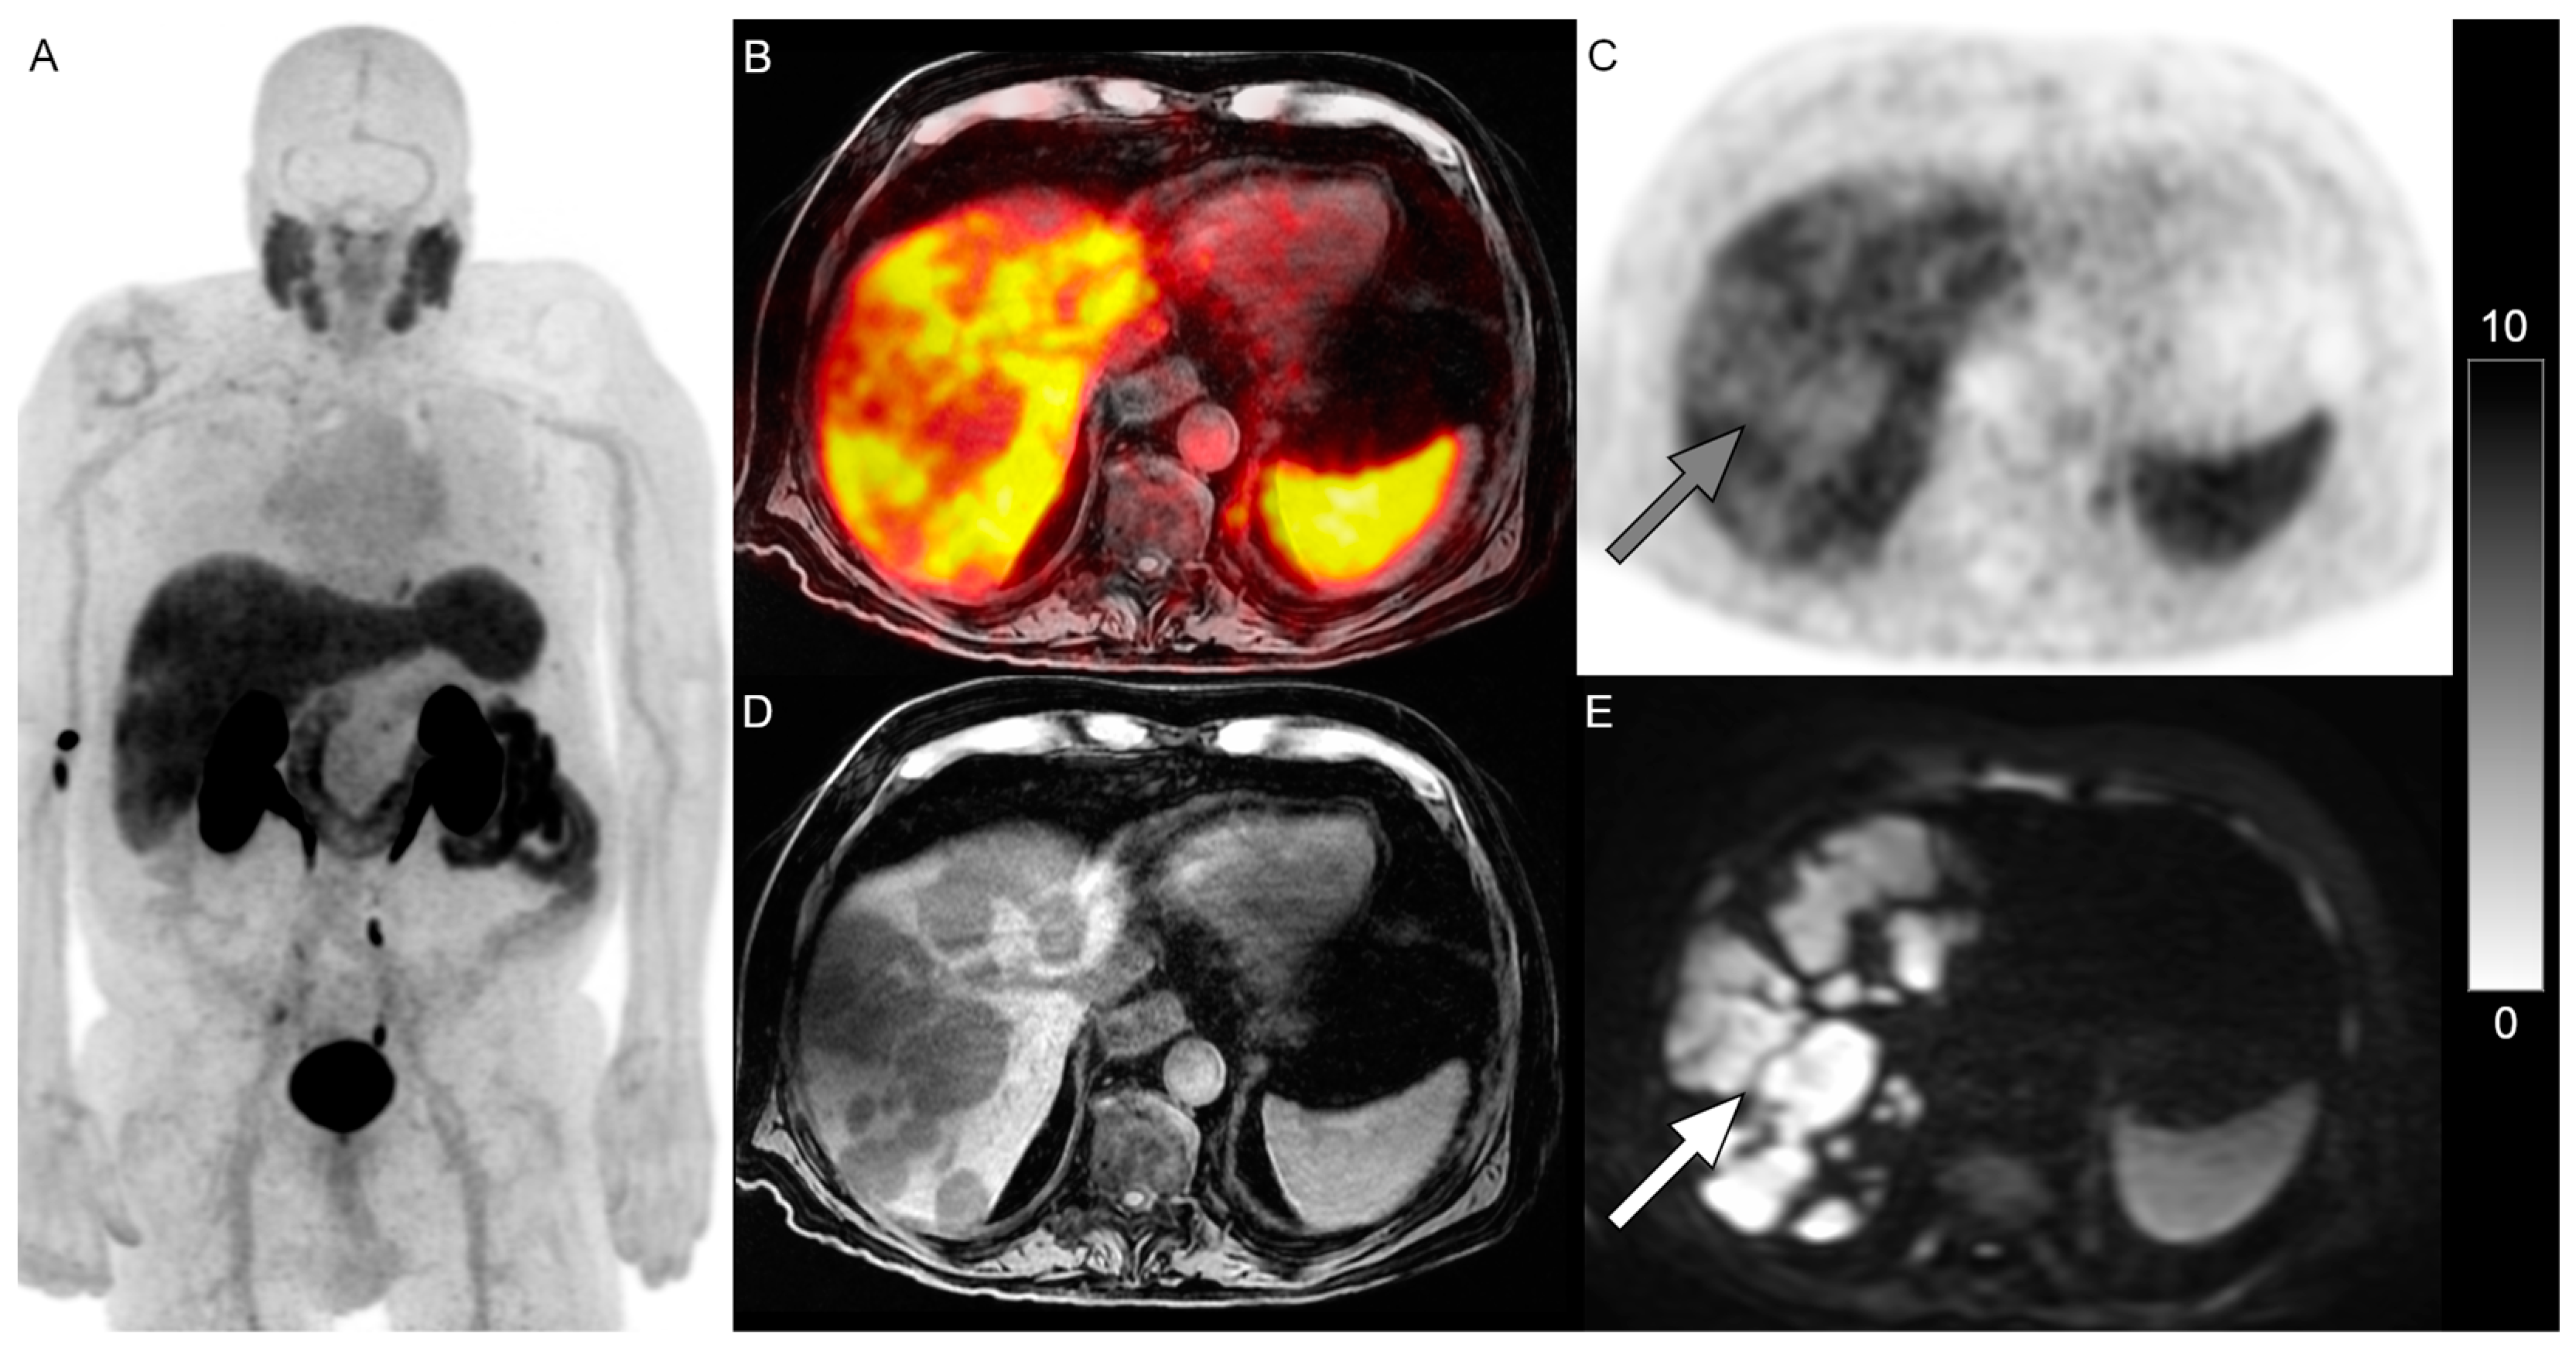

Excluding lymph nodes, DWI MRI identified additional lesions not identified on the PSMA PET in 14% (n = 6) of patients. It was noted that while 46% of patients in this analysis received RLT, none of these six patients with non-nodal mismatched disease received RLT. Figure 1 and Figure 2 show examples of patients with PSMA-negative disease that were identified on DWI.

Figure 1. PET/MRI in a 78-year-old man with mCRPC with disease progression on cabazitaxel. Whole-body 18F-DCFPyL PSMA PET maximum-intensity projection image (A) shown. Extensive PSMA-negative hepatic metastases ((B), fused image, (C), gray arrow, PSMA PET) are identified on T1-weighted image (D) and b = 800 DWI ((E), white arrow). The scale bar of PET activity (SUVs) is on the right. Given the extent of PSMA-negative disease, RLT was not considered suitable. He died two months later.